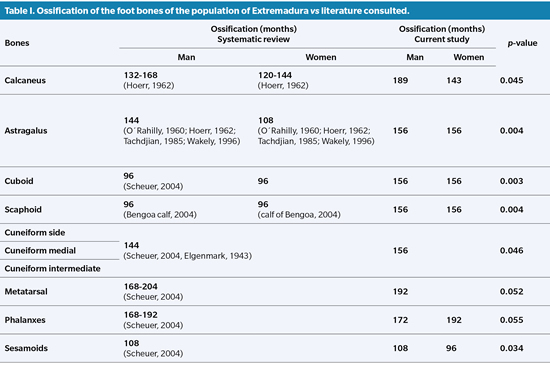

In Table I we can see the total ossification of the bones that comprise the foot, comparing the Extremaduran population against what the consulted literature dictates.

All the bones that make up the Tarsus have statistical significance in the comparison by sex with the exception of the Cuboid, the medial Cuneiform and the lateral Cuneiform. The rest of the tarsus bones have an explicit difference (P value ≤0.05) that translates into a discrepancy between the degree of ossification and its speed, later and slower for males (Table II).

Analyzing in depth the process of ossification of each one of the bones of the foot, we can begin by affirming that among the bones that form the Tarsus there are significant differences between what has been published by various authors and our results4. Regarding the Calcaneus, for example, we differ in our results regarding epiphyseal fusion at term, since our results establish it from 180 months (some 9 months later in boys than in girls), compared to ages earliest proposed by the other authors18. The talus has a bone maturation that is more similar to that established by the classical bibliography. However, complete epiphyseal fusion in the literature shows ages of 108 months in children, while in the population of Extremadura it is 156 months with 108 months and 167 months for females and males respectively19,20.

On the other hand, it is worth noting the age of total maturation of the Cuboid between 72 and 108 months in girls, compared to 60 to 96 months in boys, compared to the 96 months of age established by Seucher without differentiation by sex. This fact also happens with the scaphoid4,21.